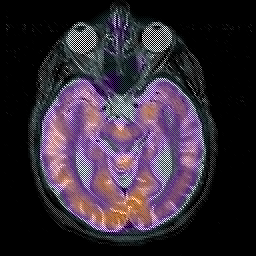

Alzheimer's disease, overlay -- Slice #19

[Home][Help][Clinical][Tour 1][Tour 2] Slice 19